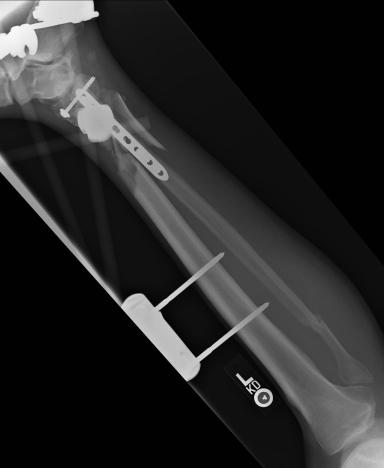

Post-corrective surgery X-Rays of the damaged right & left legs / ankles

The first two x-rays show Liam’s left ankle and pelvis prior to the accident. For comparison purposes it is interesting to see the

differences. The next x-rays were taken after the corrective surgery performed by Dr. Armendariz. Noticed that Dr. Armendariz has used tibia

bracing and also aligned the bone fragments of the left leg so that they could heal in the proper orientation. The external fixation has been

removed and Liam’s left foot has been returned to a more natural alignment.